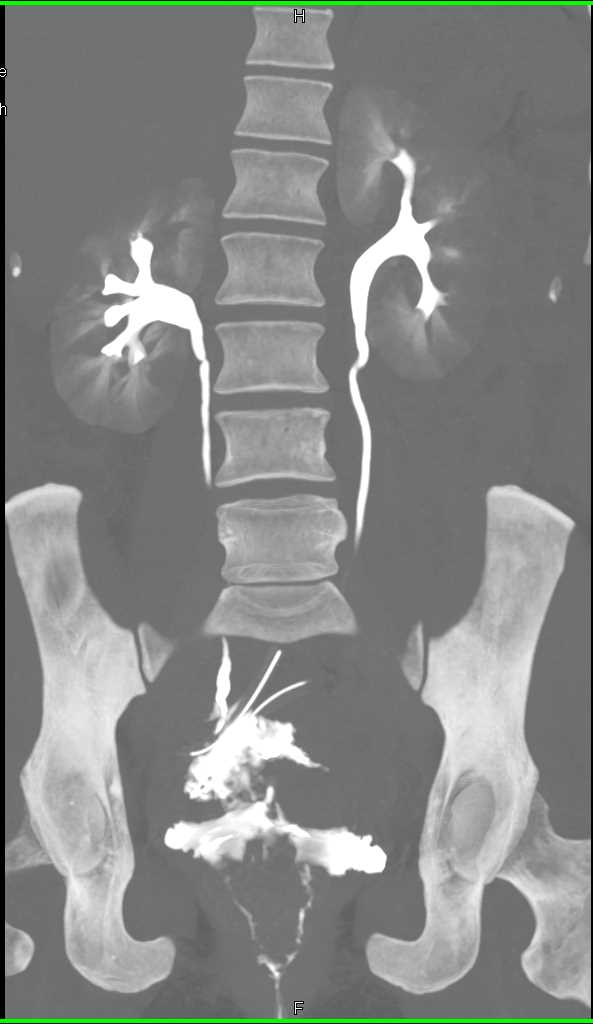

Extravasation from the Bladder